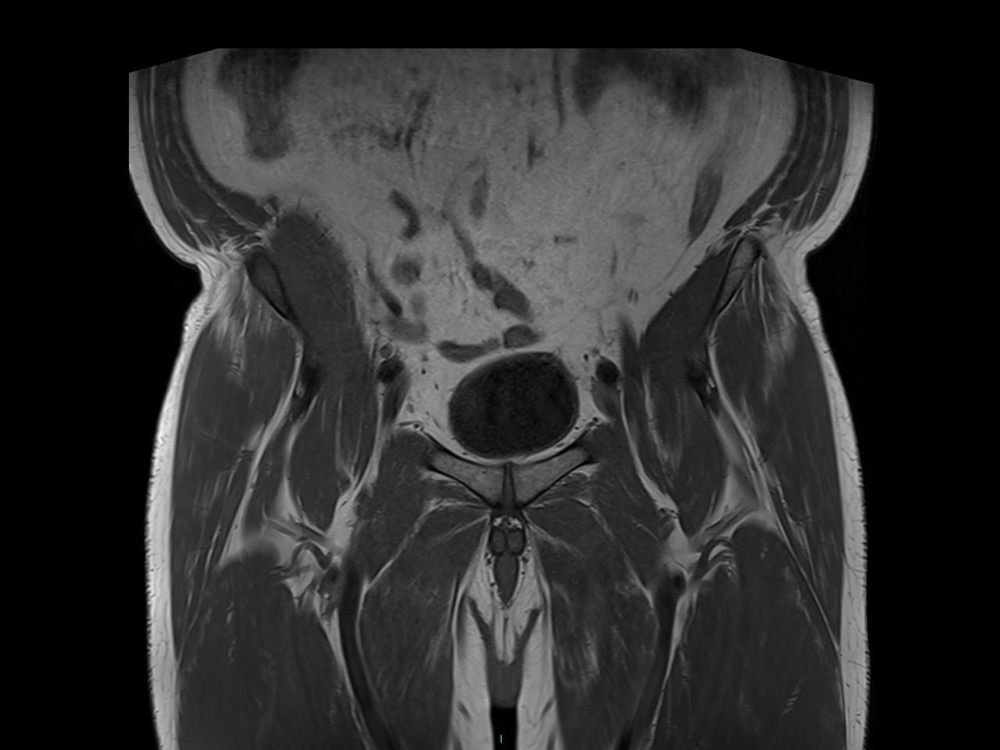

Bone Club

Olivia Fortucci 11/01/2023